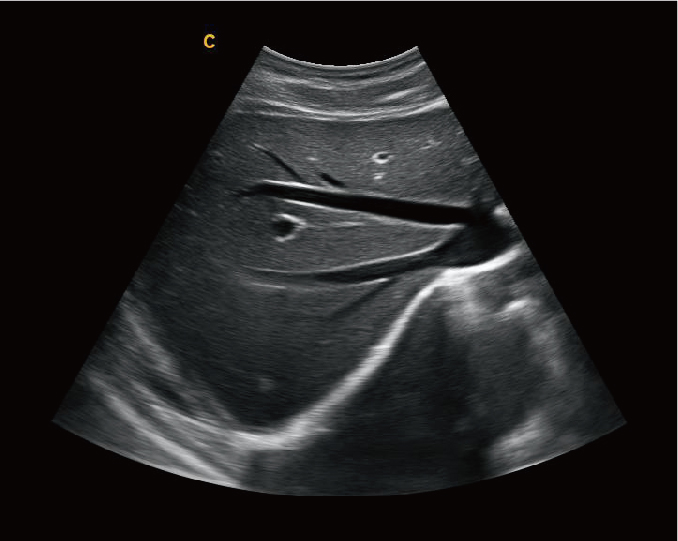

肝脏,B 模式